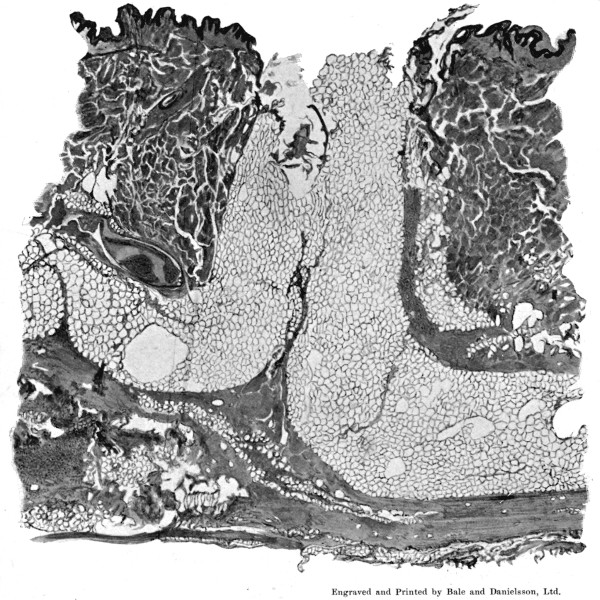

25a. Sections of Mauser Entry and Exit Wounds74

1. Section of Mauser Aperture of Entry To face p. 73

2. Section of Mauser Aperture of Exit 76